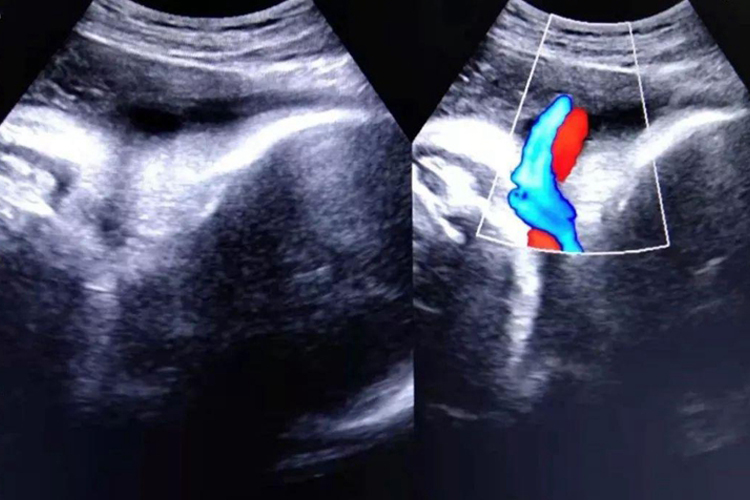

脐带绕颈属于脐带缠绕的一种,与脐带过长、胎儿小等原因相关,严重时可导致胎儿宫内窘迫,超声检查时胎儿颈部可有脐带血流信号。

此外,脐带不是足够长,脐带绕颈还会导致胎先露下降受阻,使产程延长或者停滞。超声检查时胎儿颈部可有脐带血流信号,脐带缠绕过紧,缠绕处皮肤有明显压迹,这种情况一般伴有胎动和胎心异常。